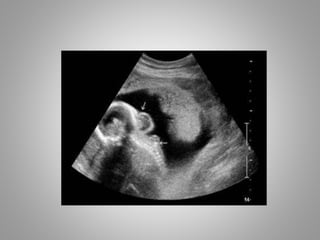

• Head changes in Open Spina Bifida

1. Ventriculomegaly……….........

2. Lemon Sign……………………….

3. Banana Sign………………………

B/L Frontal Bone Indentation

Banana Sign

Normal Cerebellum & CM

Banana shaped Cerebellum with

obliterated CM

• The banana sign and effacement of cisterna

magna are due to fluid leakage allowing

cerebellum to compress into lower posterior

fossa.

• Cerebellum hemispheres wraps around lateral

aspect of brain stem and so asumes C-shape

{Banana Shape} in transcerebellar plane.

• These sonographic findings constitute Chiari II

malformation.